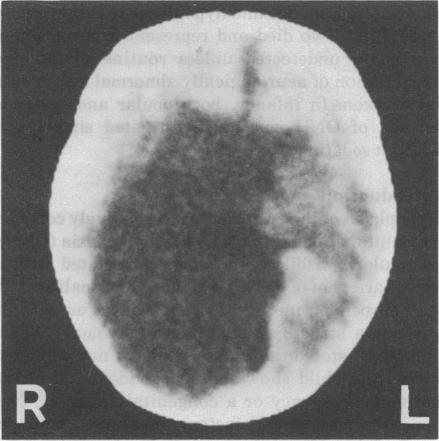

Certain features of optic nerve hypoplasia (ONH), its systemic associations and investigation are exclusive to infancy. These include the facility to use cranial ultrasound, difficulties in assessing ocular features and visual function, and neonatal hypoglycaemia and jaundice. Six infants with ONH are presented; cerebral abnormalities were demonstrated by cranial ultrasound in five. Neonatal cholestatic jaundice and hypoglycaemia occurred in one infant. Two died and represent a group likely to remain undetected unless routine ophthalmic examination of neurologically abnormal neonates is undertaken. In infancy, both ocular and systemic aspects of ONH can be investigated simply and without sedation.

视神经发育不全(ONH)的某些特征、其全身关联及检查在婴儿期具有独特性。这些包括使用头颅超声的便利性、评估眼部特征和视觉功能的困难,以及新生儿低血糖和黄疸。本文介绍了6例患有ONH的婴儿;5例通过头颅超声显示有脑部异常。1例婴儿出现新生儿胆汁淤积性黄疸和低血糖。2例死亡,这代表了一个群体,除非对神经异常的新生儿进行常规眼科检查,否则他们可能仍未被发现。在婴儿期,可以简单且无需镇静地对视神经发育不全的眼部和全身方面进行检查。